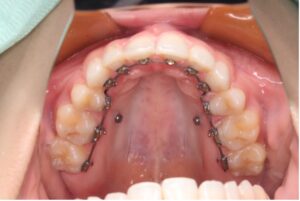

上下ともブラケットを裏側につける、もっとも見えないワイヤー矯正です。

正面からはほぼ見えないため審美性を重視したい方にはメリットが大きい矯正方法ですが、これまでの矯正装置の中で一番舌に当たりやすいため、発音がしづらく慣れるまでは強い違和感があります。また、料金も一番高価です。

〈メリット〉

・装置がほとんど見えない

・見た目を気にせずに矯正治療ができる

〈デメリット〉

・舌に違和感が出やすい

・話すのに慣れるまで時間がかかる

・費用が他に比べると高くなる

・装置が裏側についているため歯磨きがしづらい